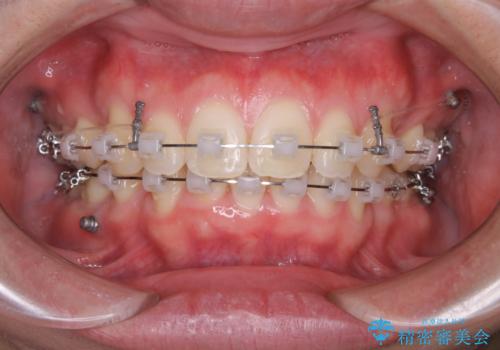

- 矯正装置

- ワイヤー矯正 審美装置

突出感とがたつきの改善を行うために大きなスペースが必要であったため、親知らず以外の歯を4本歯を抜歯する計画を立てました。

移動量が大きいこと、また、患者さんの生活習慣的にマウスピース装着が難しそうとの理由から

ワイヤー表側矯正装置で治療を行うことになりました。